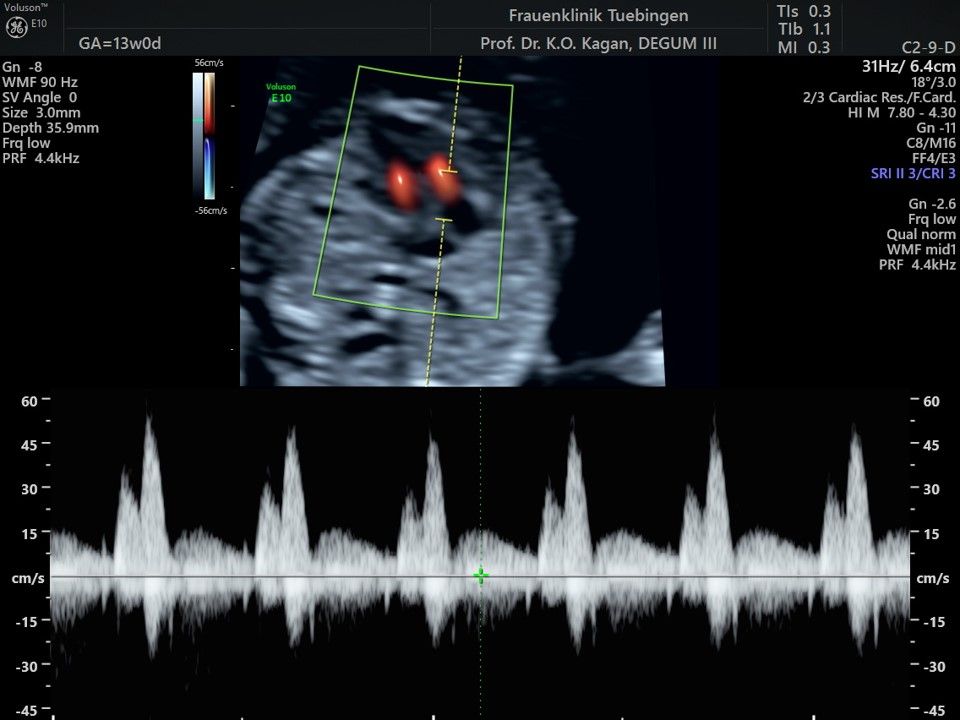

Herz

Mithilfe des Ersttrimester-Screenings kann das persönliche Risiko einer Präeklampsie bestimmt werden. Dazu wird die Vorgeschichte der Schwangeren, der aktuelle Blutdruck, das Ergebnis der Ultraschalluntersuchung (Widerstand in den Gebärmutter-nahen Gefäßen) und der Blutabnahme bei Ihnen (PAPP-A) kombiniert. Sollte das Risiko über 1:100 sein, empfehlen wir die tägliche Einnahme von Aspirin 150mg bis zu 35.SSW und eine gezielte Überwachung der weiteren Schwangerschaft.

Das Ergebnis der Ultraschalluntersuchung ist wegweisend. Dabei wird der Fet vermessen, die Organe werden untersucht und die sonographischen Marker zur Risikoberechnung für Chromosomenstörungen werden beurteilt. Das sind: die Nackentransparenzdicke, Nasenbein sowie der Blutfluss in der rechten Herzhälfte und im Ductus venosus, einem Gefäß in der Leber des Feten.